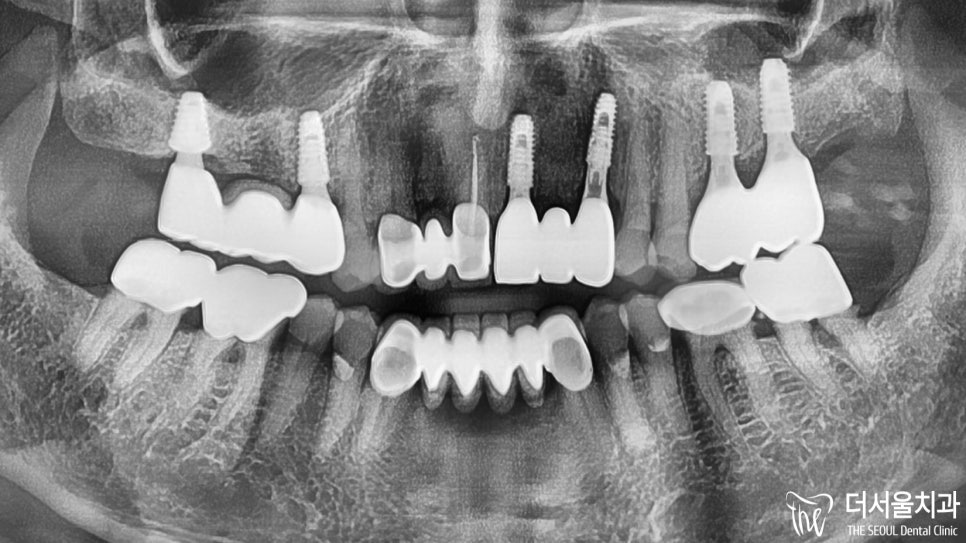

더서울에서는 말씀드렸던 내용을 토대로

치조골 소실이 꽤 심한 상태였기 때문에

이식하는 자체에도 어려움이 있었는데요.

모자란 곳에 보강을 해준 뒤,

5개월의 기간을 두어

회복을 기다리기로 했습니다.

5개월 뒤,

치아가 없는 부위가 빵빵해지면서

골이식이 된 것이 확인이 되네요~

픽스쳐 식립까지 문제 없이 마무리 되었습니다.

이후 앞니 임플란트 의 최종 단계인

크라운 제작 만을 남겨둔 상황입니다.

좀 더 예쁘고 심미적인 형태 재현을 해야 되기에

손이 더 많이 가는 작업인데요ㅎㅎ

언제나 그랬듯이 잘 해드렸습니다.

예전에 # 26 # 27 치료도 더서울에서 하셨는데

3년이 지난 지금까지 잘 사용하고 계시네요.

이번 전치부 보철도 튼튼하게 잘 사용하셨으면 좋겠습니다^^